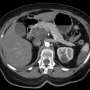

The pancreas, a vital gland located behind the lower part of the stomach, performs essential functions such as producing hormones that regulate blood sugar and enzymes that aid in digestion. However, when it develops cancer, early symptoms can often be overlooked or mistaken for other conditions.

Latest data shows that pancreatic cancer has one of the lowest survival rates among all cancers, with only about 10% of patients surviving five years post-diagnosis. This alarming statistic underscores the necessity for public awareness of warning signs that can lead to timely medical intervention.

What to Watch For: Experts highlight several key symptoms that individuals should be vigilant about, including unexplained weight loss, jaundice (yellowing of the skin and eyes), abdominal pain, and changes in appetite. If you experience any of these symptoms, it is crucial to seek medical advice immediately, as these could be indicative of pancreatic cancer.